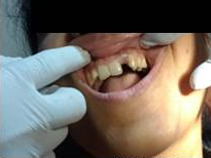

Pre Operation

Placement of Bone Grafting